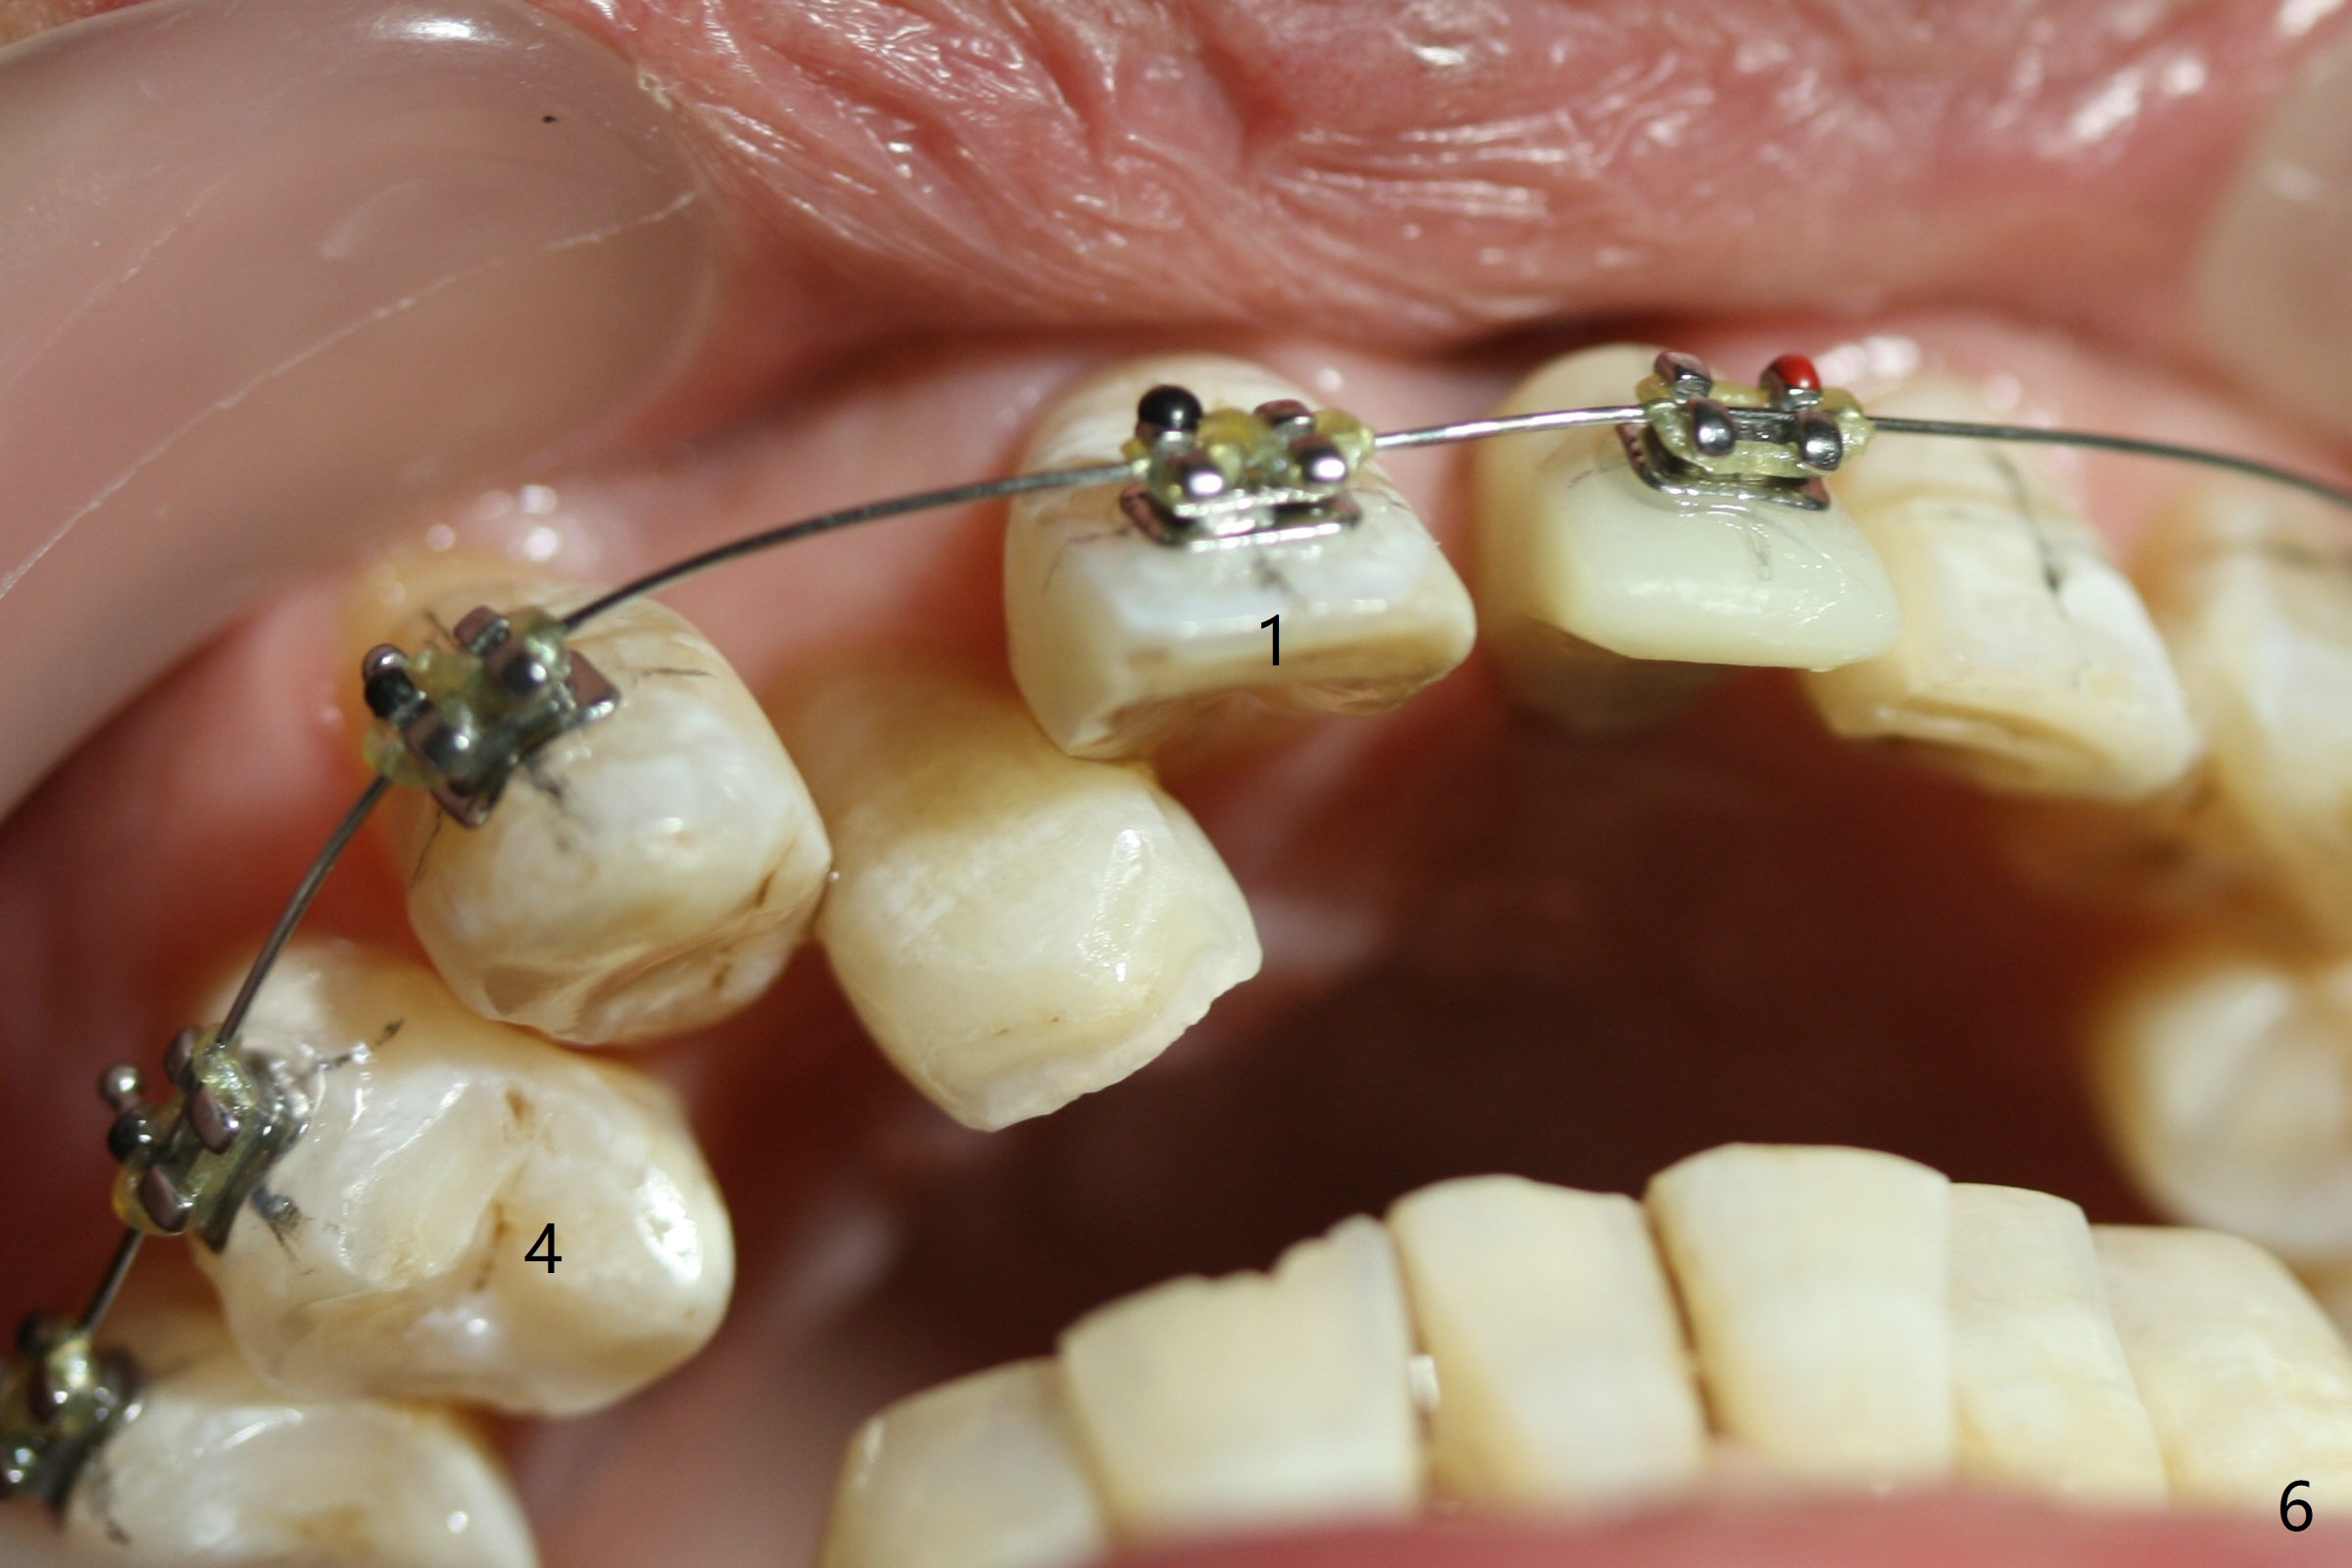

Limited Ortho with Proximal

Reduction

Nearly 7 months postop, the immediate provisional at UL1 is removed; with the mesial reduction of UL2 from 7 to 6 mm (Fig.1), an angled abutment is to be changed (4.5x15 degree, 2 mm cuff). A new provisional (Fig.2,3) co-incides with the facial midline. Brackets will be placed between UR4 to UL3 except UL2 (symptomatic once with chronic periodontitis) with initial proximal reduction between UR1-4 in preparation to correct cross bite of UR2. Twelve days later, the patient returns for UR5-UL3 bracketing after UR1-4 initial proximal reduction with 14 niti wire (Fig.4-6). UR1 moves mesial 20 days post open coil spring (Fig.7 arrow), while UL1 debracketes after permanent re-cementation of the temporary crown last visit (*, no re-bracketing, since it appears not essential). Before placement of 20 ss wire, diastemata are created by proximal reduction (Fig.8 *). In fact UR1 moves mesial, while UR3 does not move distal with the open coil. With placement of UR6 (implant) molar band, UR3 is distalized effectively. With sling shot, UR2 is almost labialized in one appointment (Fig.9). After consolidation of the diastemata between UR1-6 with power chains following UR2 cross bite correction (Fig.10), the restoration space for UL1 seems to be too large (Fig.11). Next visit, check the midlines, take 1-2 PAs for #7-9 and determine whether a straight abutment should be changed back and whether composite should be placed UR1 mesial to reduce the space. One week later, composite is added to the mesial surface of the tooth #8 to increase its width, while the provisional at #9 is relined to improve the interdental papilla (Fig.12). Minimal bone loss at UR2 is observed 8 months post banding (Fig.13), while the socket at UL1 seems to have healed except the most coronal 1 year 3 months postop (Fig.14 *). The margin of the abutment should be uneven, more coronal proximal than buccopalatal (Fig.15). The final crown has an open margin, partially due to less ideal trajectory (Fig.16 (black line: ideal trajectory, nearly 1 year 4 months postop)). Guided surgery could solve the problem. Sticky bone may restore the buccal plate defect. Die shows that the implant is palatally placed (Fig.17). CT will be taken to determine whether the implant perforates the palatal plate.